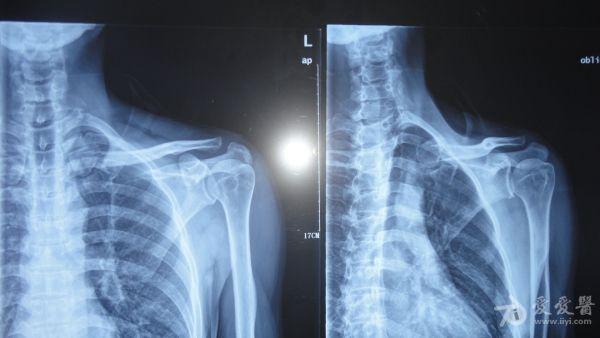

患者**,男,43岁,2个月前因不慎摔伤致左锁骨内侧骨折,行保守治疗,锁骨、前臂吊带固定。定期拍片复查,最近一次X片示骨折断端内侧向后上移位,外侧向前下移位。于12月20日诊断以“左锁骨骨折骨不连2月余”入院。专科检查:左锁骨压痛叩击痛,外形畸形,肩关节活动受限。昨日在臂丛下行骨折切开复位内固定术,用三枚克氏针固定。大家看一下,讨论讨论有什么更好的办法吗?受伤时

入院时拍的